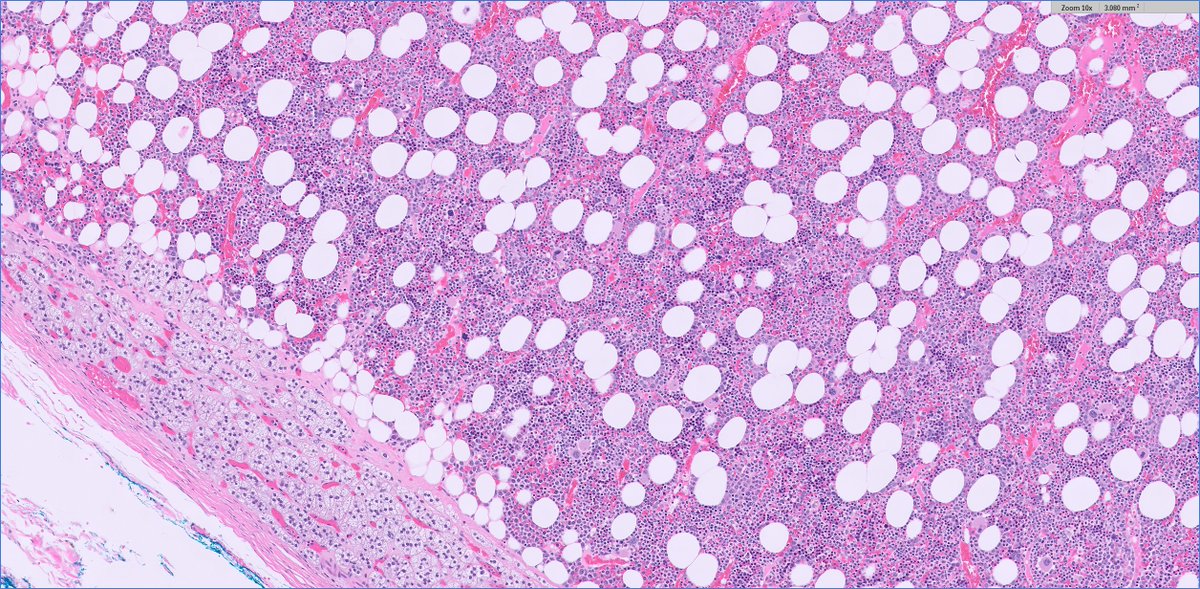

#endopath: adrenal myelolipoma

adrenal myelolipoma